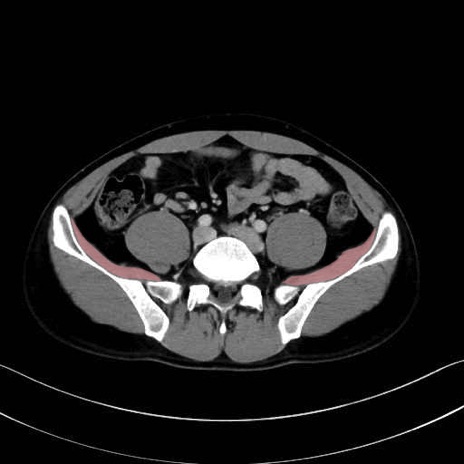

腸骨筋 (Iliacus)